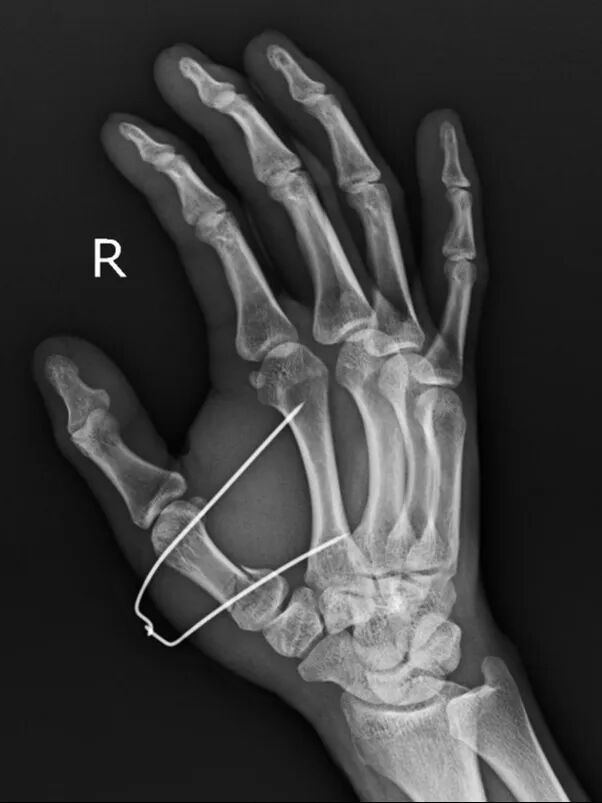

患者是52歲男性,因摔倒導致右手第一掌骨基底部骨折

手術前右手正斜位片

手術后次日復查左手正斜位片